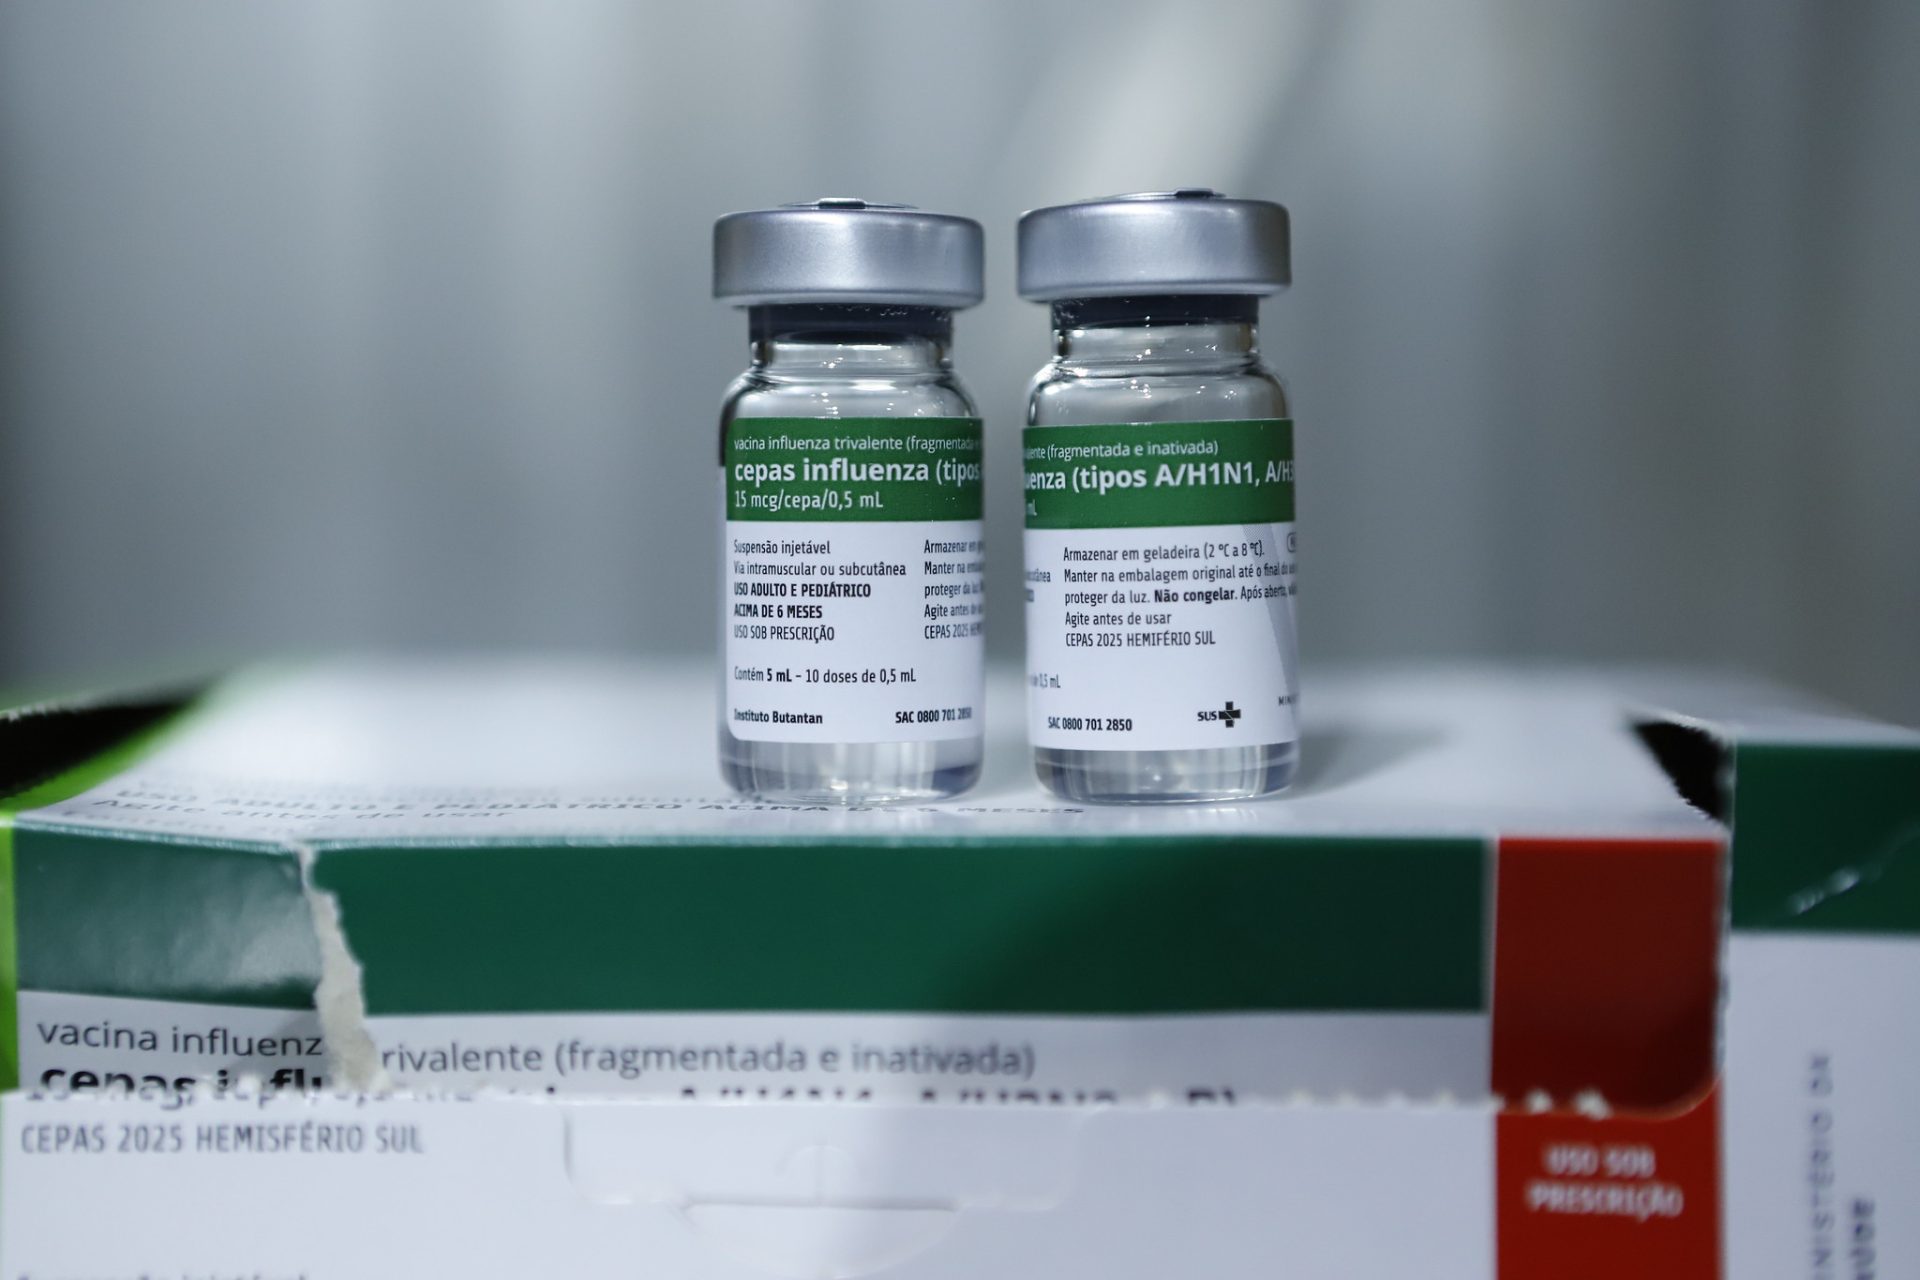

Mais de 100 salas estão disponíveis para vacinação contra gripe no DF

Saúde do DF inicia aplicação da vacina contra gripe nesta terça-feira (25)

Esta semana marca o início da aplicação da vacina contra a gripe no DF. São…

A partir desta terça-feira (25), a vacina contra a gripe (influenza) estará disponível em mais de…